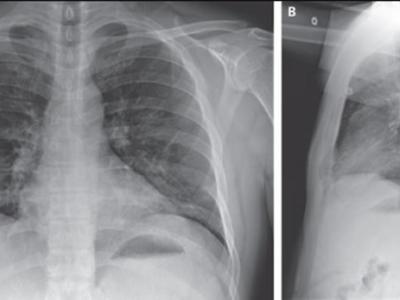

患者住院第6天的胸部X光(蜘蛛网eeook.com报道)据ETtoday(詹雅婷、丁维瑀):各国...